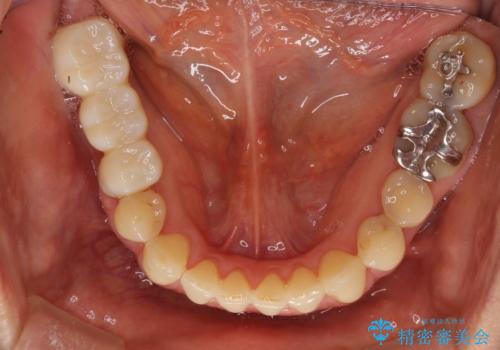

反対咬合や欠損を治療したい インビザライン矯正とオールセラミックブリッジ

- 虫歯治療がうまく進まないとのことで来院された患者様です。

虫歯治療や欠損補綴治療も必要でしたが、前歯が反対咬合であったので、セラミッククラウンやブリッジによる治療と並行して矯正治療を提案しました。

仕事柄海外出張が多いとのことで、虫歯治療後にインビザラインにて矯正治療を行うこととしました。